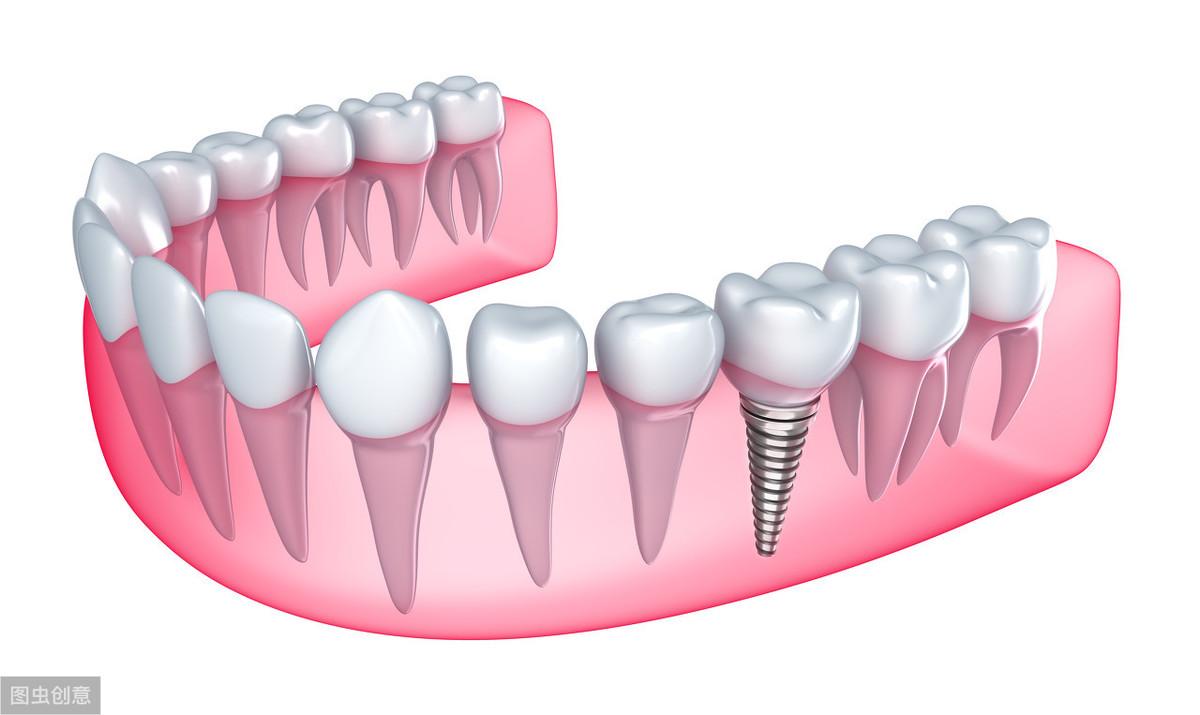

種植牙技術是近幾十年出現(xiàn)在大眾視野中的一種修復缺失牙體的方法。一顆完整的種植牙體由三部分組成:種植體、基臺、人工牙冠。

手術過程就是將種植體植入患者的牙體缺失處,待其傷口愈合,種植體與牙槽骨結合牢固后,將基臺安裝在種植體上,再將人工牙冠安裝在基臺上,形成完整而堅固的人工牙體。